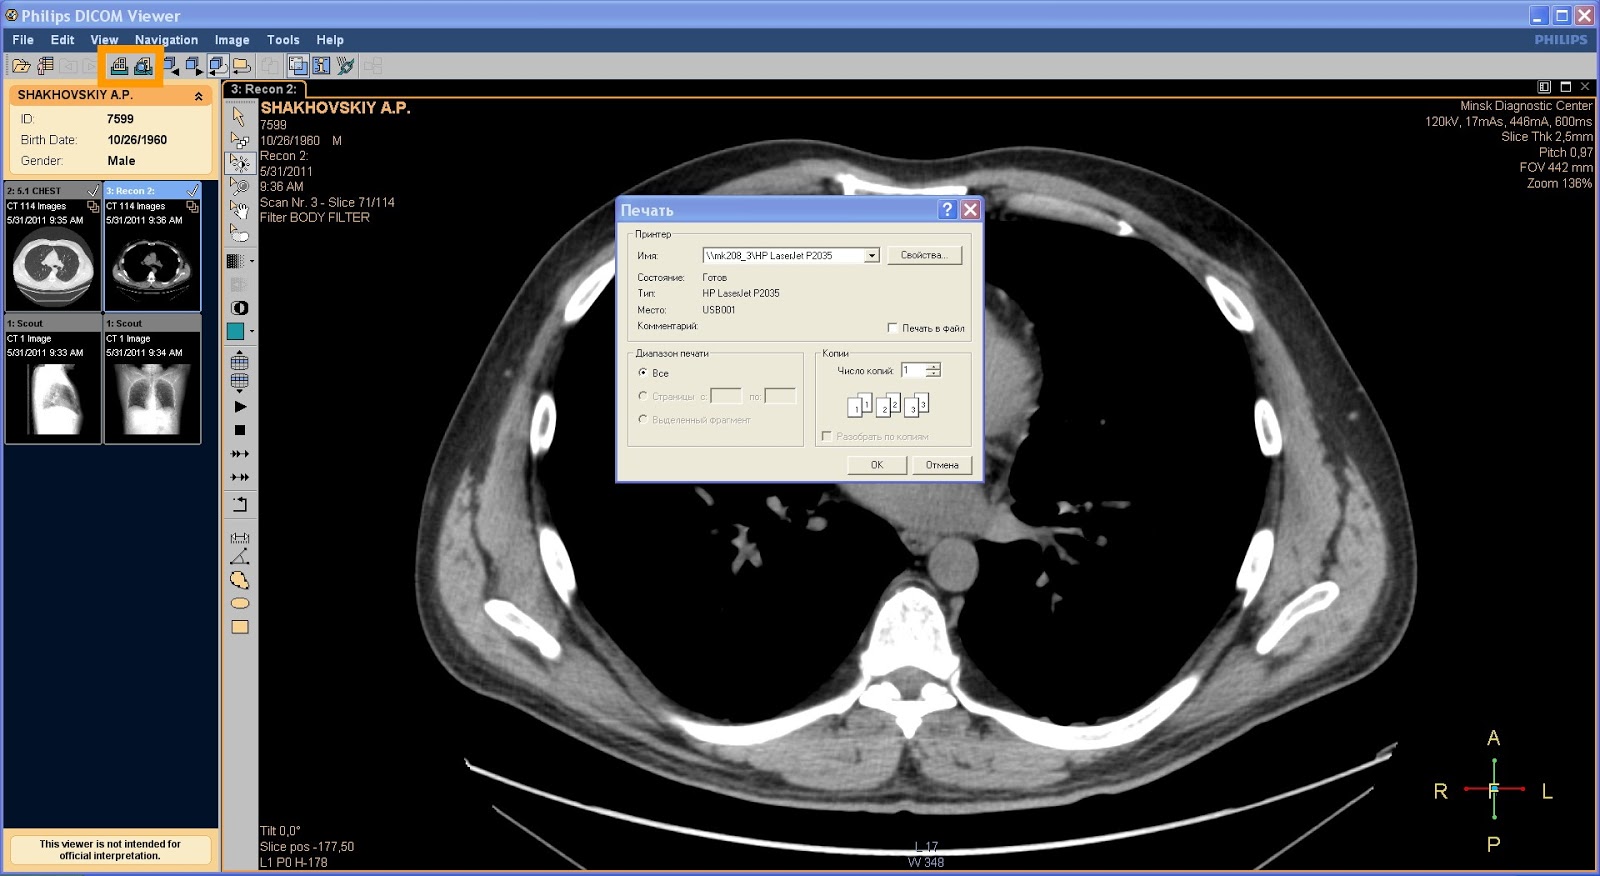

Лазерная камера для печати медицинских изображений на пленке стандарт dicom